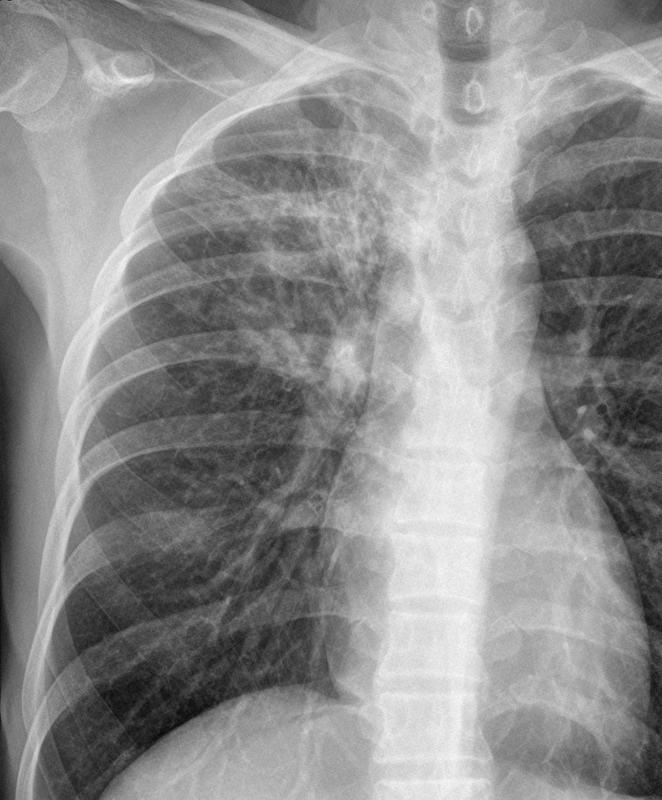

active TB